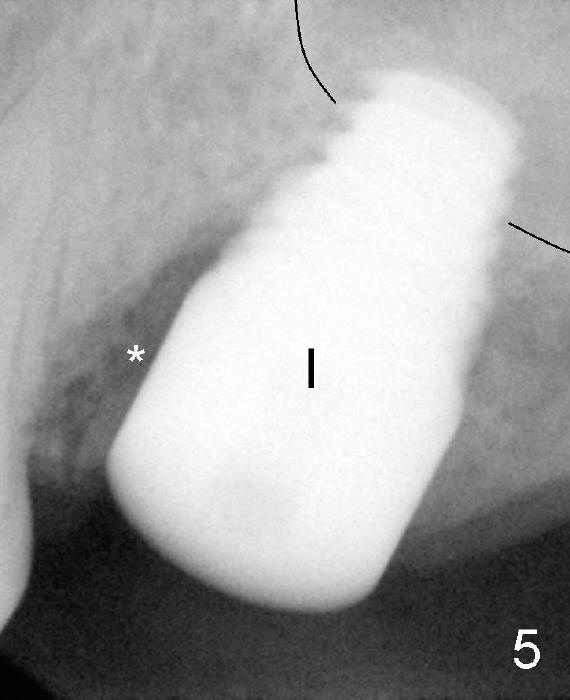

Fig.9 (5.5 months post implantation, immediately post cementation of the crown (C). The mesial socket has apparently decreased in size and increased in density.

Black line: sinus floor.